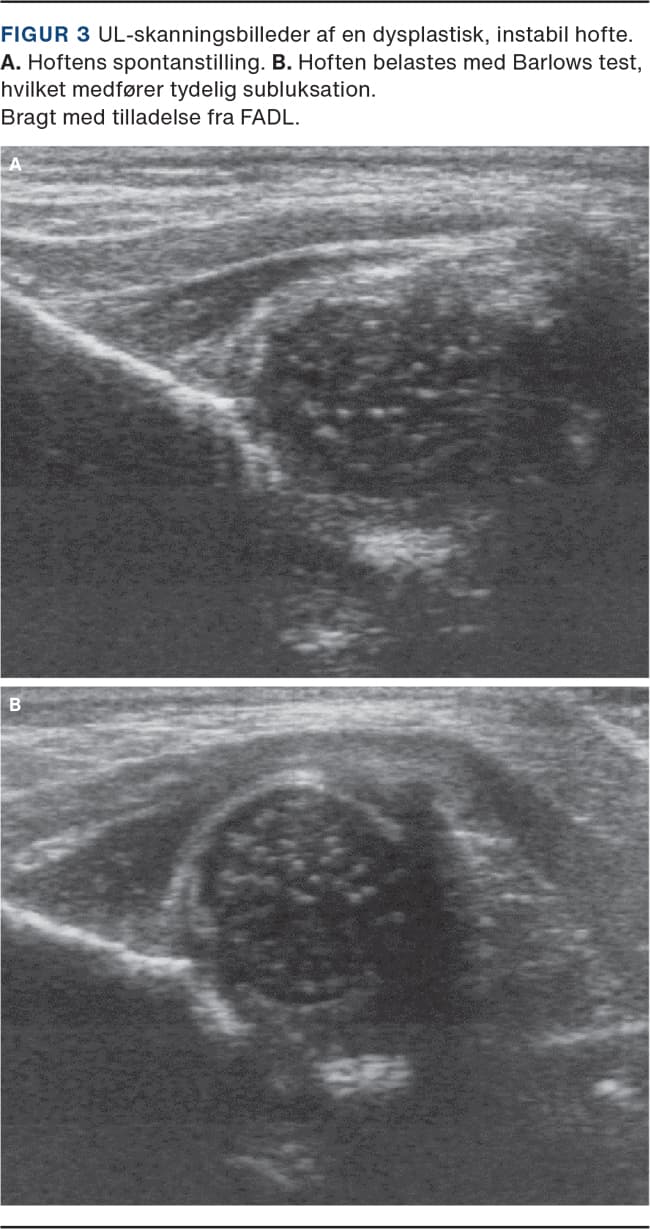

Hoftedysplasi diagnosticeres ved en kombination af klinisk stabilitetsundersøgelse og billeddiagnostik. Den kliniske undersøgelse baseres på Ortolanis og Barlows håndgreb samt Galeazzis tegn. Fælles for håndgrebene er, at undersøgeren påviser en ustabilitet eller luksation i hofteleddet hos barnet. Derudover undersøges hoftens passive bevægelse med særligt fokus på abduktionen. Billediagnostisk er UL-skanning førstevalg hos mindre børn (< 6 måneder), hvor kernen i caput femoris endnu ikke er ossificeret. Ved UL-skanning undersøges acetabulums anatomi, og det er samtidig muligt at teste stabiliteten i hofteleddet (Figur 2 og Figur 3). Efter påbegyndt ossificering af caput femoris kan leddet ikke visualiseres sufficient med UL-skanning, og røntgenoptagelse af bækkenet er derfor førstevalg.